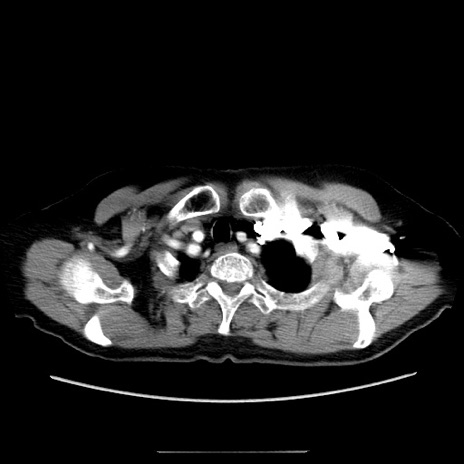

症例5(横断像)

【症例】70歳代女性

【主訴】お腹が張る

【現病歴】1週間くらい前から腹部膨満の自覚あり。昨日夜から増悪したため、本日救急外来受診。

【身体所見】意識清明、BT 36.5℃、BP 165/106mmHg、HR 80bpm、SpO2 98%、腹部:膨満、軟、自発痛・圧痛なし、触診にて不快感あり、腸蠕動音:減弱

【データ】WBC 12600、CRP 1.04